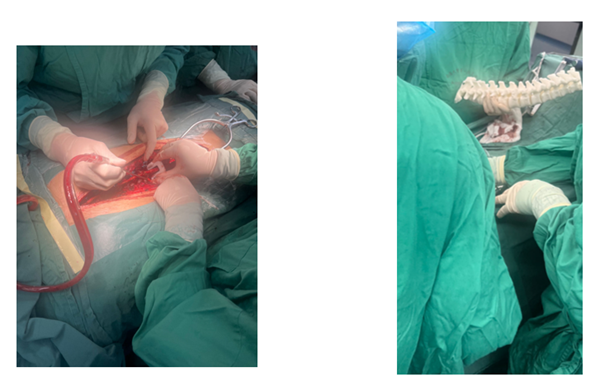

△術(shù)中圖片及術(shù)后CT效果圖

數(shù)字醫(yī)學(xué)中心提供的寰樞椎置釘定位導(dǎo)板在進(jìn)行椎弓根釘?shù)闹踩胧中g(shù)時,按照術(shù)前CT檢查提供的影像數(shù)據(jù),調(diào)整椎弓根外展角和矢狀角椎管軸心線的角度與椎弓根外展角和矢狀角的角度相適應(yīng),通過開路進(jìn)行鉆孔,探針檢測鉆孔無誤后即可置入椎弓根釘。該瞄準(zhǔn)器準(zhǔn)器操作方便,能準(zhǔn)確進(jìn)行椎引根釘植入角度的定位。